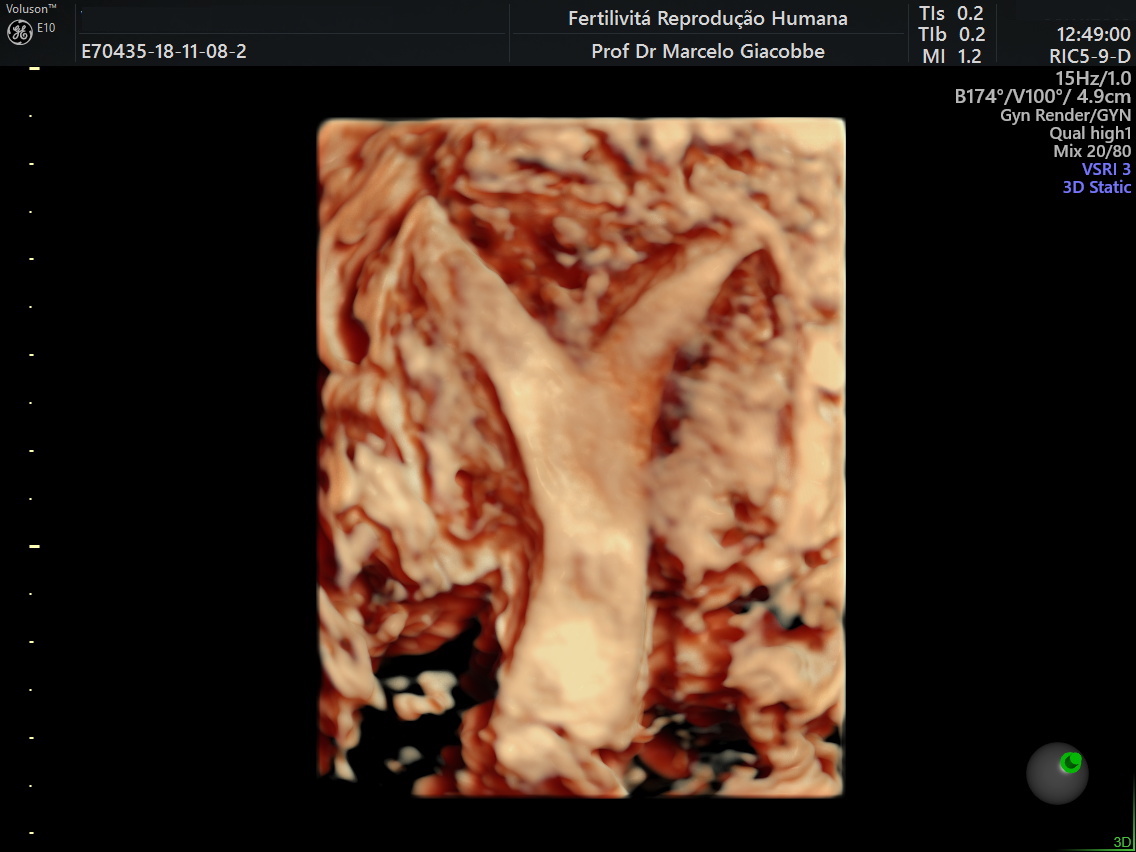

Imagens de ultrassom 3D

Útero Normal

Útero Unicorno

Útero Arqueado

Útero com Septo Longitudinal Parcial

Útero com Septo Longitudinal Completo

Útero em forma de letra T (“T Shapped”)